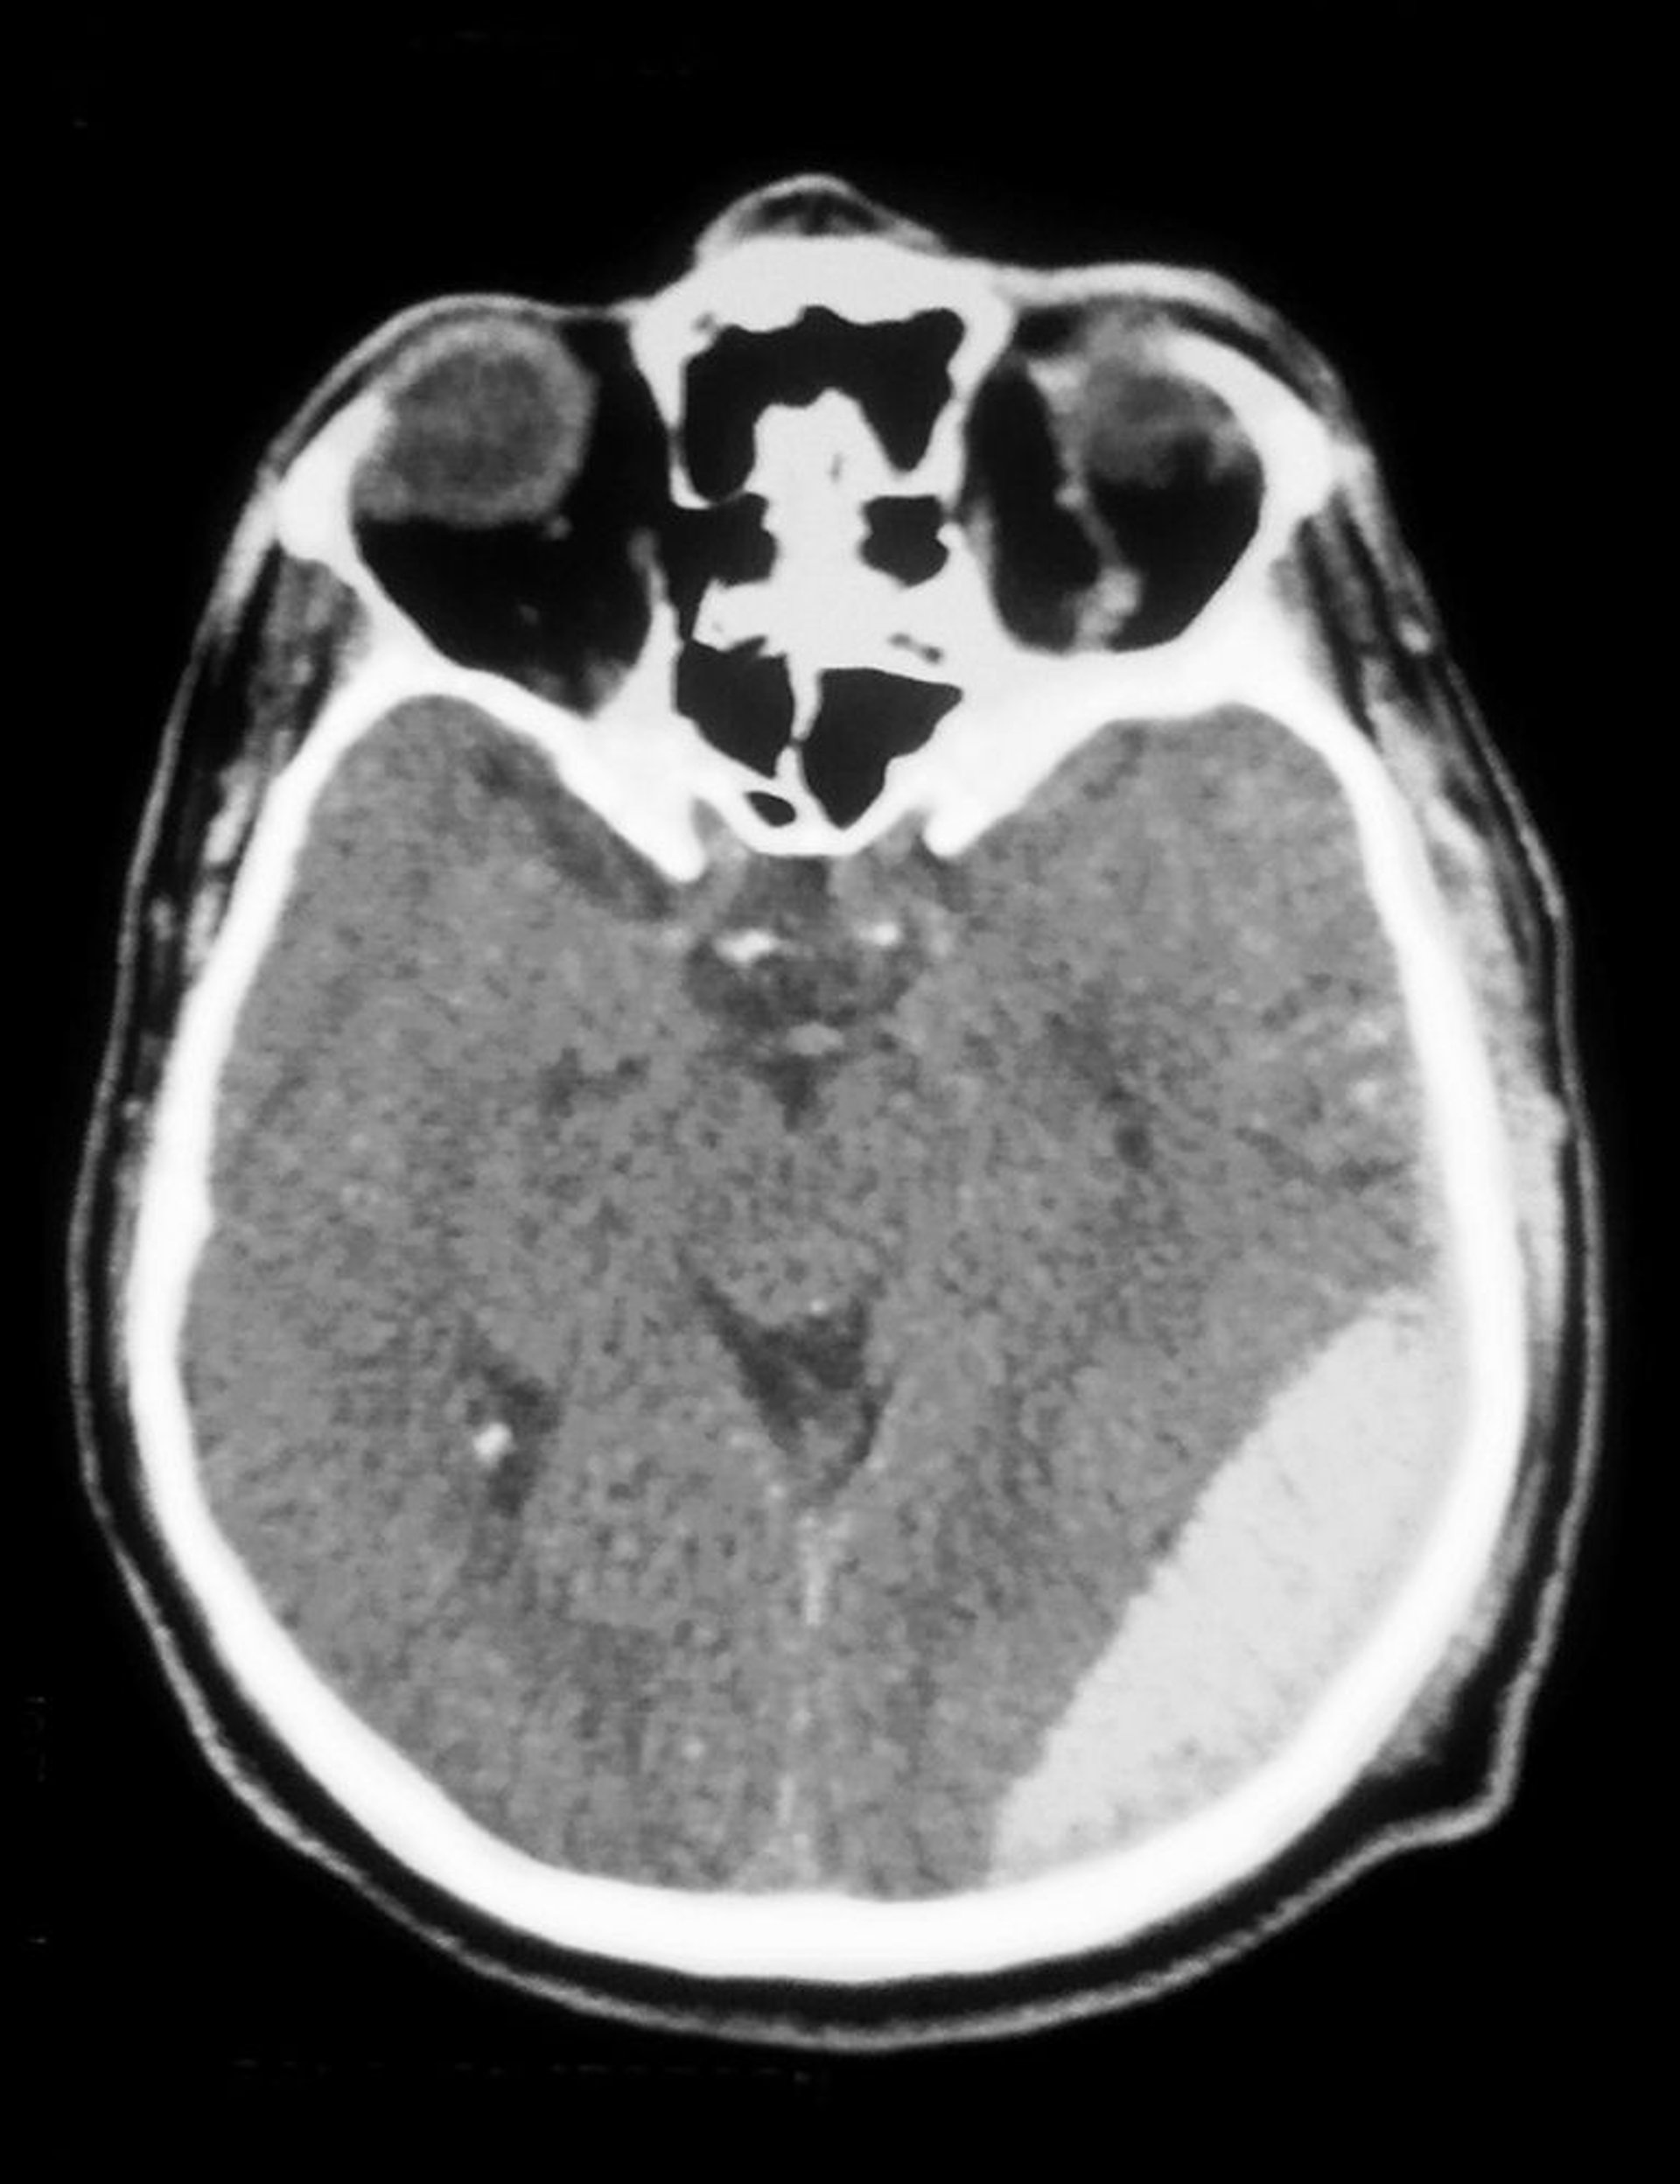

Tụ máu ngoài màng cứng

Chụp CT cho thấy một khối máu tụ ngoài màng cứng (mờ đục ở phía dưới bên phải).